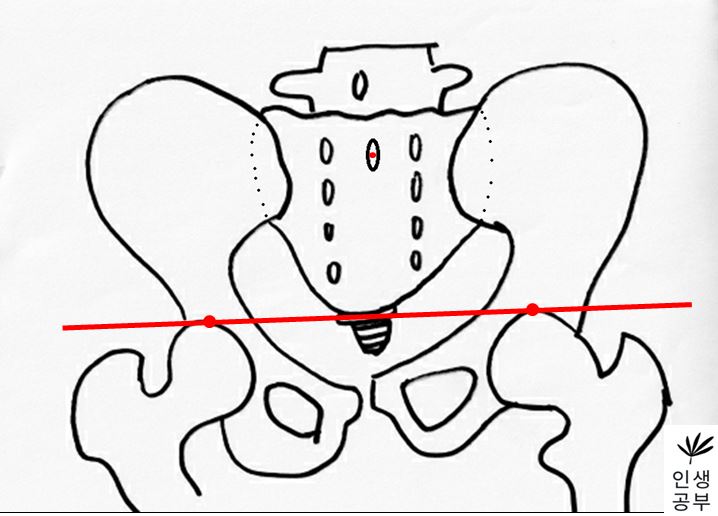

4) 1번째나 2번째 엉치뼈 결절(sacral tubercle) 정가운데 점을 찍어줍니다.

5) 치골결합(pubic symphysis) 정가운데에도 점을 찍어줍니다.